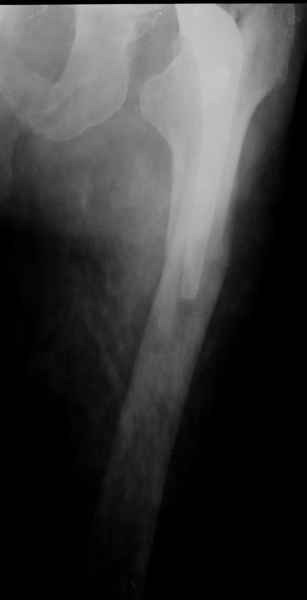

Хочется показать два подобных случая, П-ка З. 72 лет и п-т Г. 80 лет. Сразу принимаю замечание, что это были ножки цементной фиксации, просто под руками не было бесцементника.